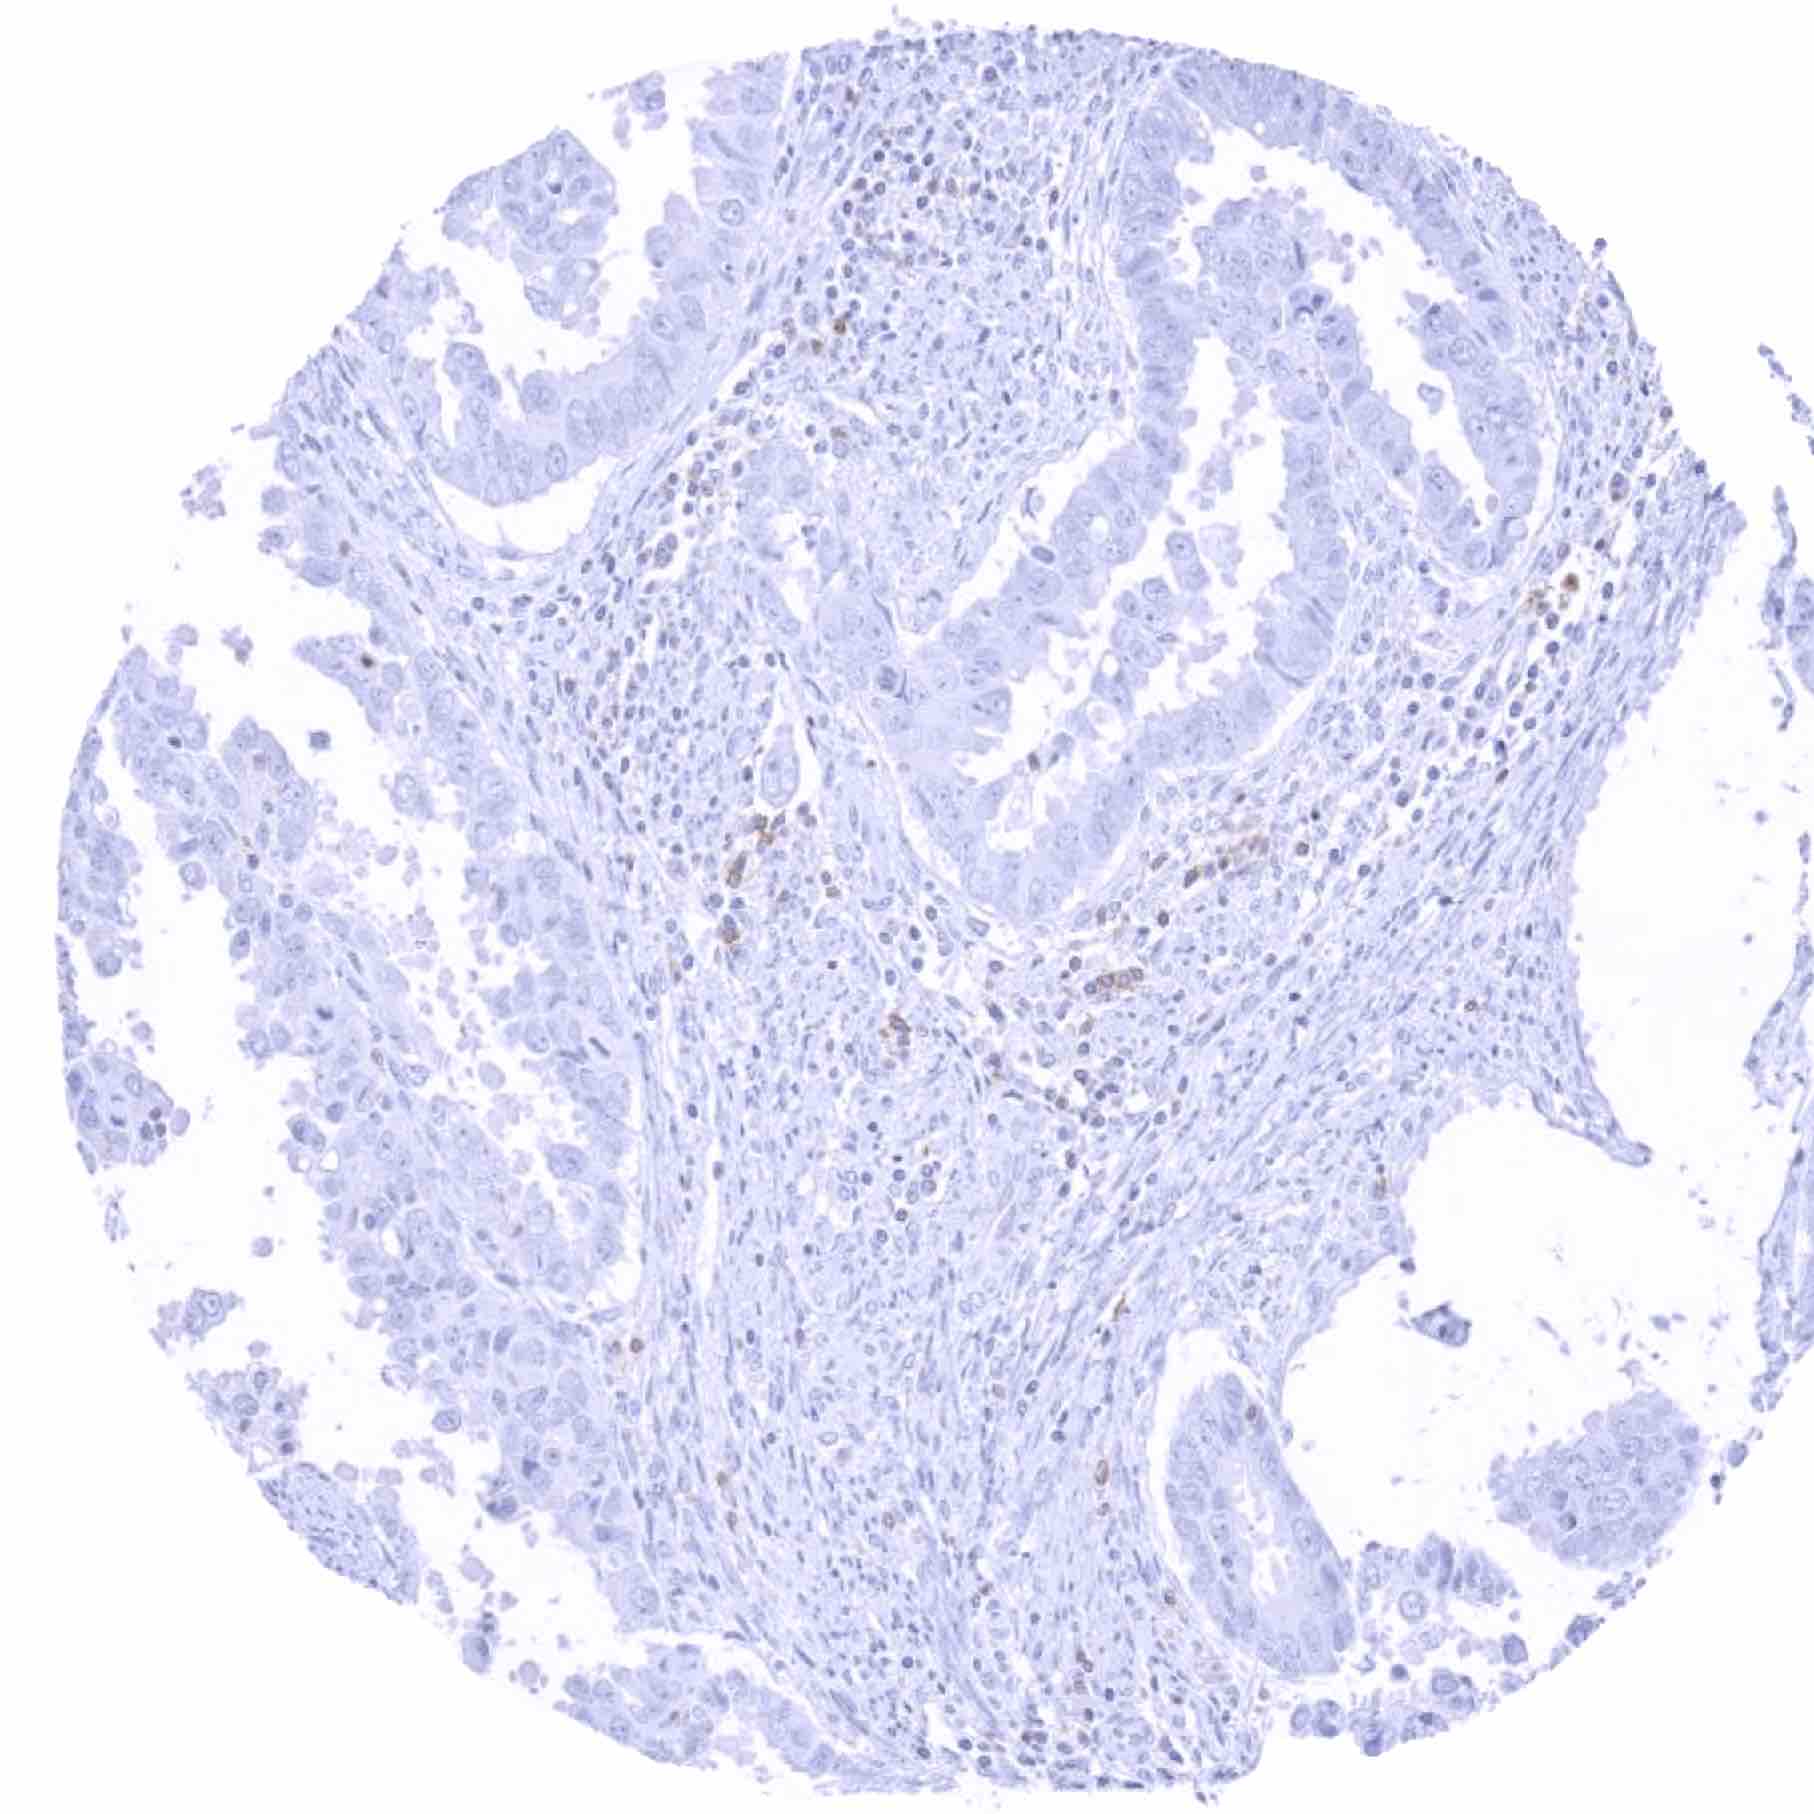

Uterus, cervix – Squamous cell carcinoma with a weak TIGIT positivity of a fraction of tumor infiltrating lymphocytes

Uterus, cervix – Squamous cell carcinoma with distinct TIGIT positivity of a small fraction of tumor infiltrating lymphocytes